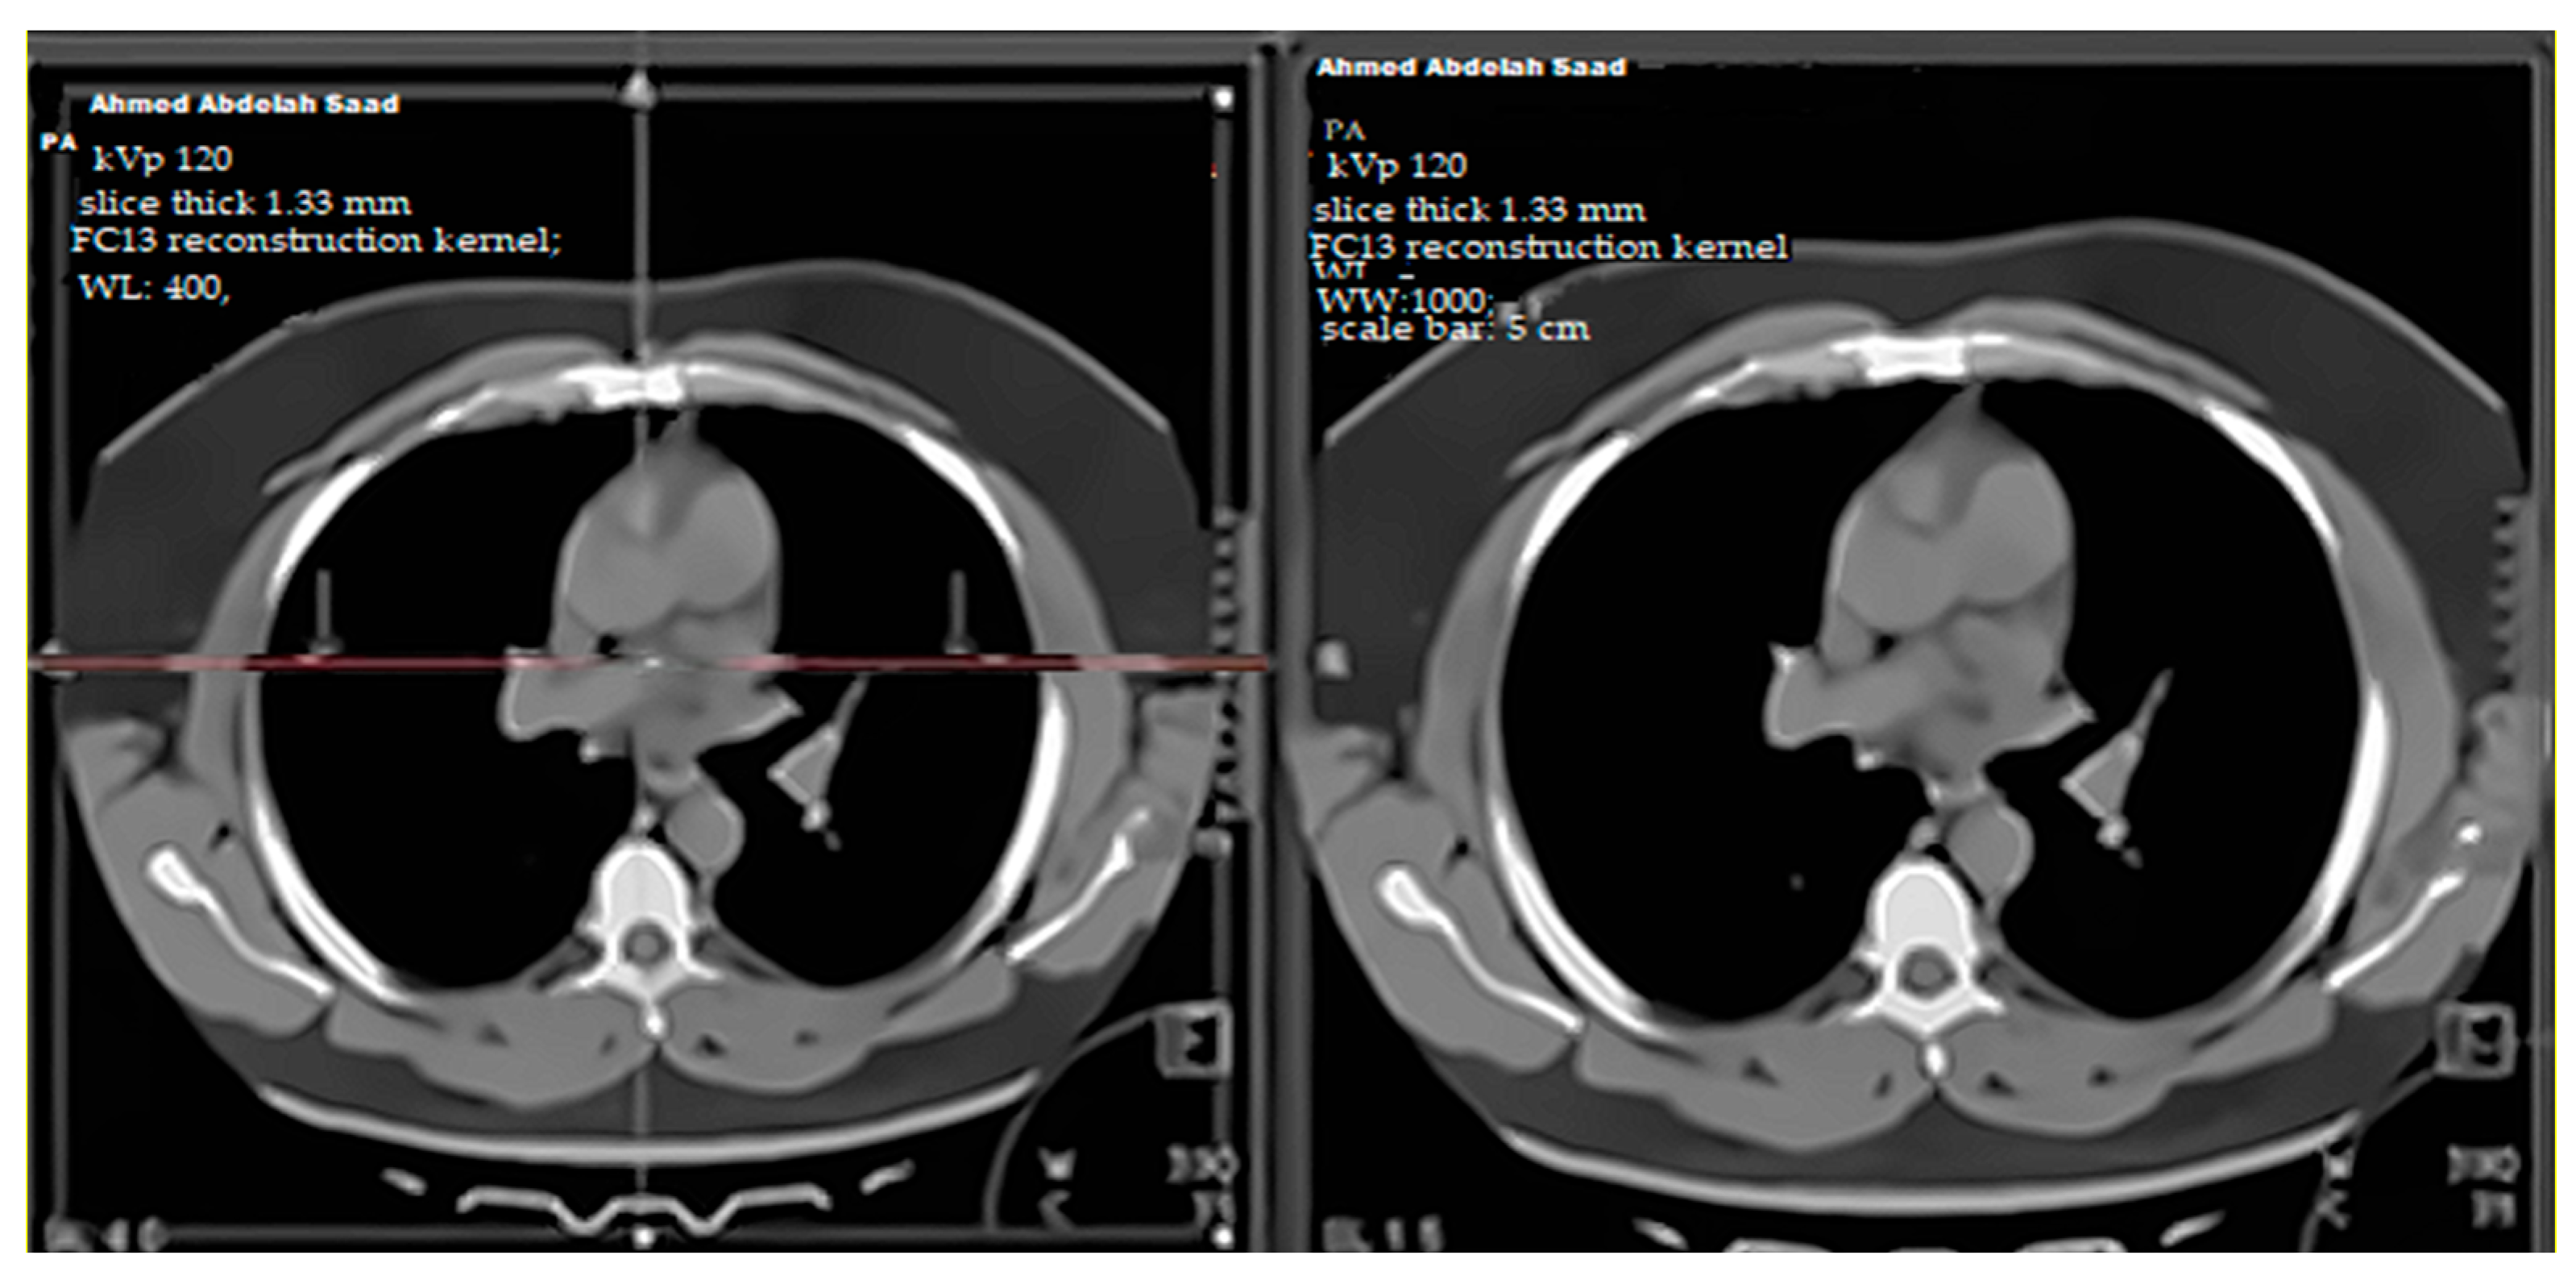

4.6. Visual Findings and Clinical Implications